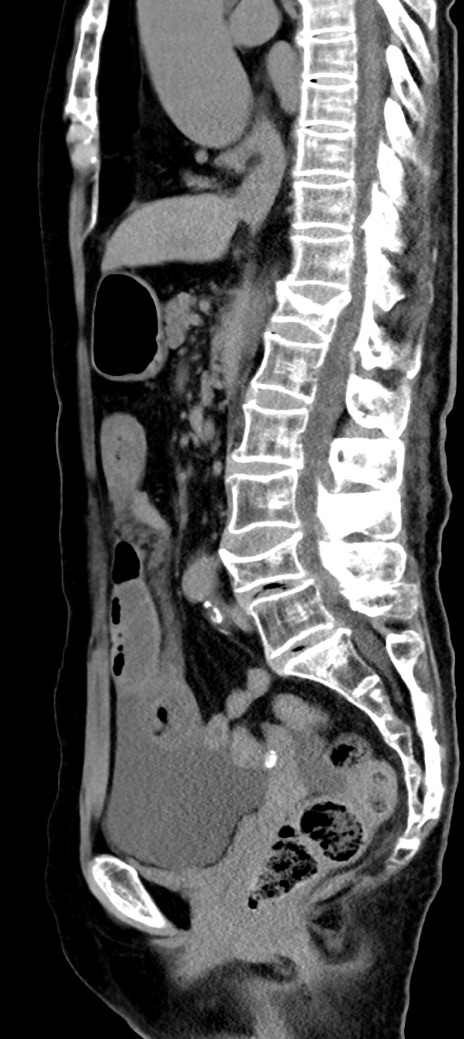

症例40(矢状断像)他院1日前

【症例】90歳代女性

【主訴】腹痛・嘔吐

【現病歴】 食欲低下、嘔吐があり昨日他院受診。肺炎と診断され入院となる。入院後より腹部全体に圧痛あり。胃管留置され経過みていたが、症状持続するため、

当院転院となる。

【既往歴】胸椎圧迫骨折、胆石症

【身体所見】腹部:中央に激痛あり、圧痛あり、反跳痛不明

【データ】WBC 17100、CRP 18.82